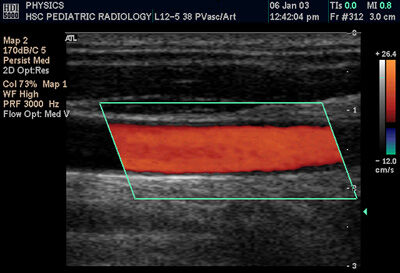

Colour Doppler of Common Carotid Artery

Sonography can be enhanced with Doppler measurements, which employ the Doppler effect to assess whether structures (usually blood) are moving towards or away from the probe, and its relative velocity. By calculating the frequency shift of a particular sample volume, for example a jet of blood flow over a heart valve, its speed and direction can be determined and visualised. This is particularly useful in cardiovascular studies (sonography of the vasculature system and heart) and essential in many areas such as determining reverse blood flow in the liver vasculature in portal hypertension. The Doppler information is displayed graphically using spectral Doppler, or as an image using color Doppler (directional Doppler) or power Doppler (non directional Doppler). This Doppler shift falls in the audible range and is often presented audibly using stereo speakers: this produces a very distinctive, although synthetic, pulsing sound.